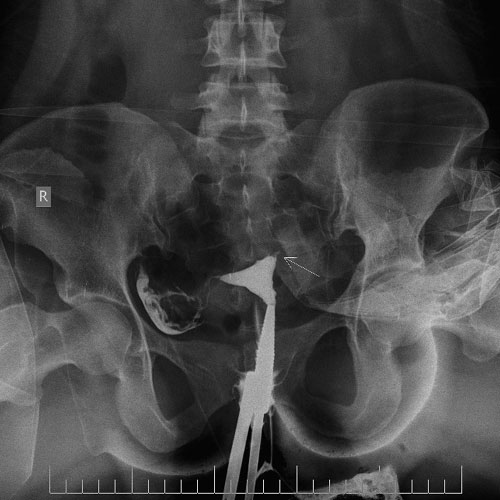

22 year old female with primary infertility. HSG showing blocked tubes on left side.